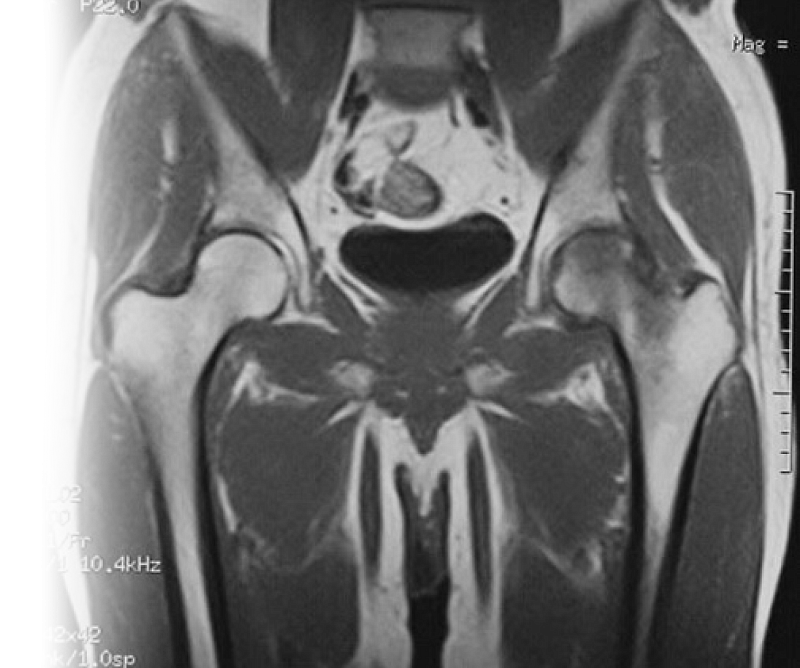

Магнитно-резонансная томография тазобедренныхсуставов – важный метод исследования, который позволяет визуализировать проксимальные отделы бедренных костей, вертлужных впадин, лонных костей, мышц, связок, сухожилий.

Также МРТ тазобедренных суставов может выполняться с дополнительными импульсными последовательностями (на усмотрение врача-травматолога).